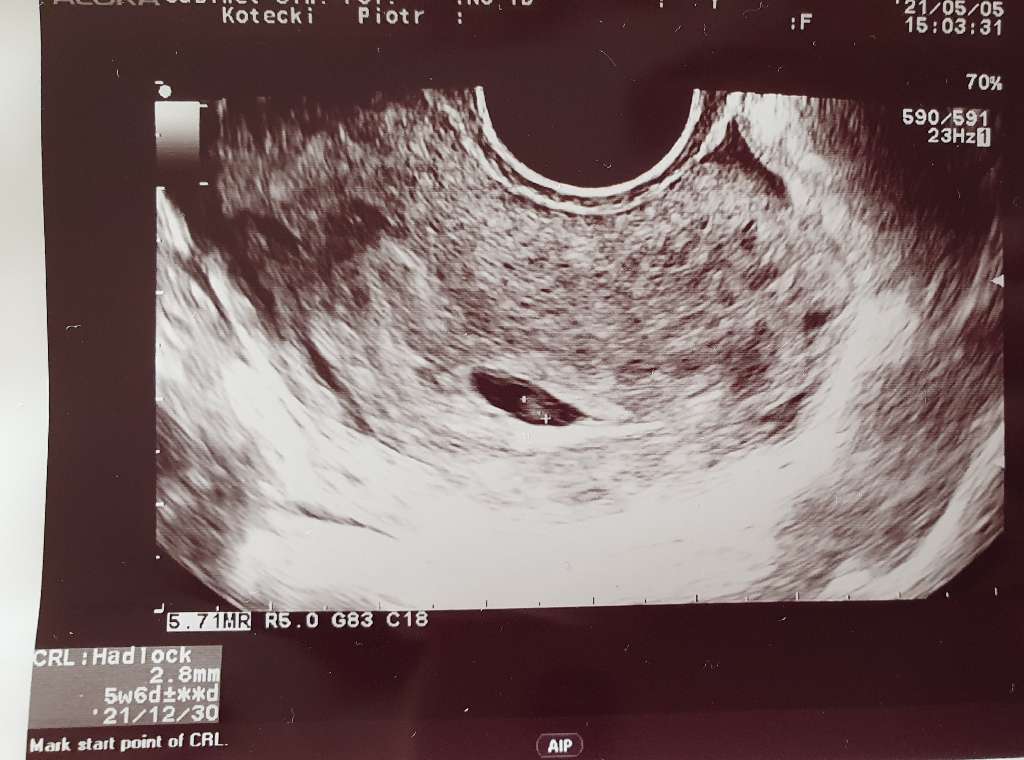

Z wielkością zarodka miałam podobnie, byłam w 6+2 wg ostatniej miesiączki, na USG było dzieciątko z bijącym serduszkiem, ale miało tylko 2mm. Lekarz mi w opisie napisał "ok. 5 tydzień". Strasznie mnie to zestresowało, bo pierwszą ciążę poroniłam, a lekarz też mnie nie uspokoił, nie założył karty ciąży, powiedział, żebym jeszcze nie robiła badań i poczekała 2 tygodnie na rozwój wydarzeń. Nie wytrzymałam i poszłam następnego dnia prywatnie na samo USG, i się okazało, że dzieciątko ma 4,5mm, serduszko bije 150/min i wszystko jest w porządku. Więc często to kwestia sprzętu

Ja bylam w 6+6 i serduszka nie bylo, nawet mowila ze zarodka bardzo nie widzi tylko pecherzyk zoltkowy no ale jak zobaczylam w zdjecia usg to jest zmierzone crl i 2,3 mm pisze i juz zgupialam czy byl zarodek czy nie, w kazdym razie ciaza wyglada na tydzien mlodsza i kolejne usg 13 maja i mowila ze wtedy powinno byc juz wszystko widac no a jak nie bedzie to wiadomo co dalej...